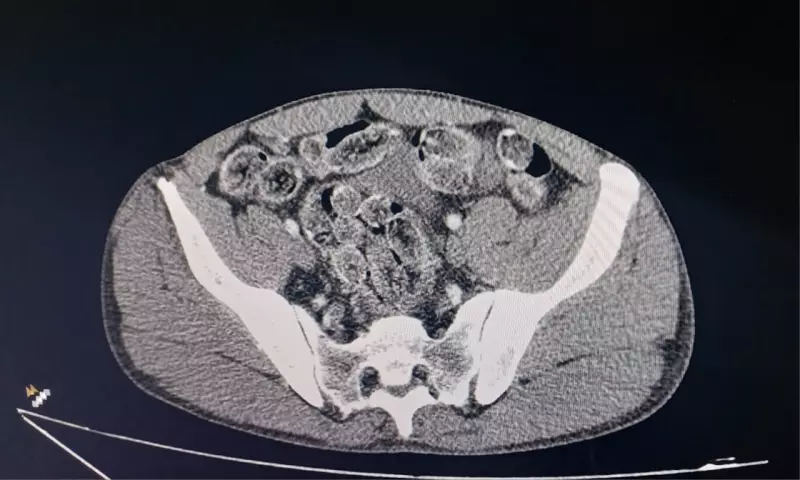

Devido à ingestão da droga, os dois homens foram rapidamente encaminhados ao Conjunto Hospitalar de Sorocaba (CHS) para avaliação e tratamento médico. Exames realizados no local confirmaram a presença de cápsulas no estômago de ambos, necessitando de intervenção clínica.

Os pacientes passaram por procedimentos médicos específicos para a expulsão do material ingerido e, atualmente, permanecem em observação hospitalar para monitoramento de possíveis complicações. A situação destaca os riscos graves à saúde associados ao consumo e transporte de drogas dessa natureza.